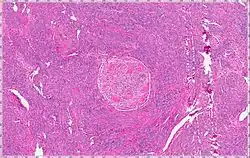

Intravenous leiomyomatosis is a rare condition seen exclusively in women in which leiomyomata, benign smooth muscle tumors, are found in veins. The masses are benign-appearing but can spread throughout the venous system leaving the uterus and even cause death when growing into the heart from the IVC.[1] While the possibility that these arose de novo from the smooth muscle in the blood vessel wall was considered, chromosomal analysis suggests a uterine origin.[2] Intravenous leiomyomata are usually but not always associated with uterine fibroids, and tend to recur.